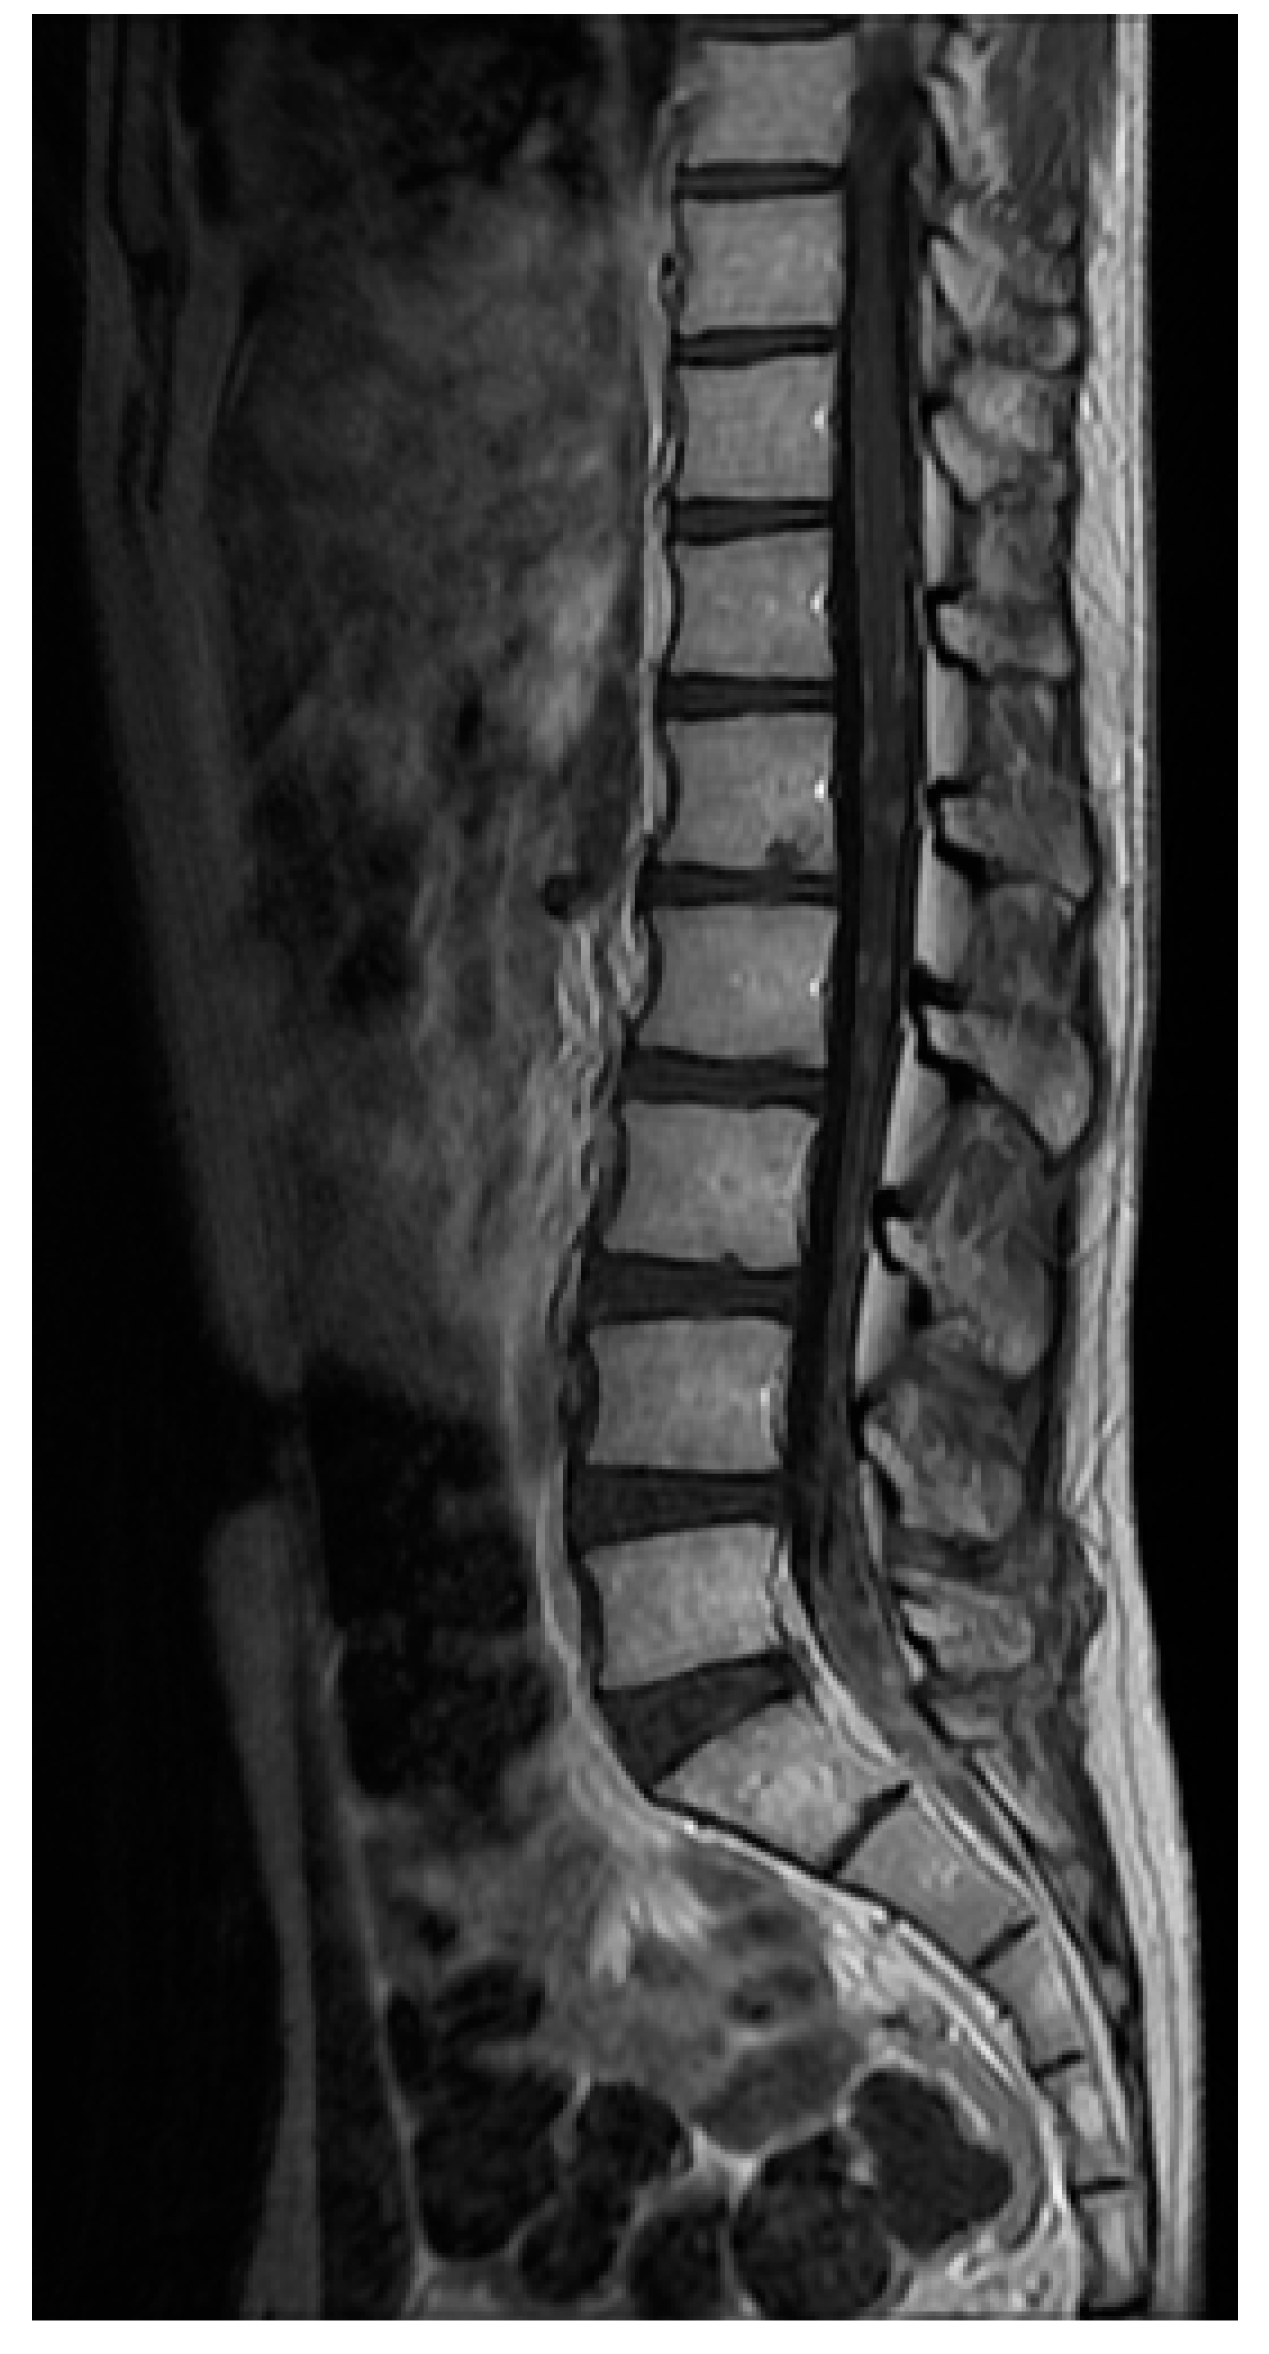

4.2. Neuroimaging Assessment